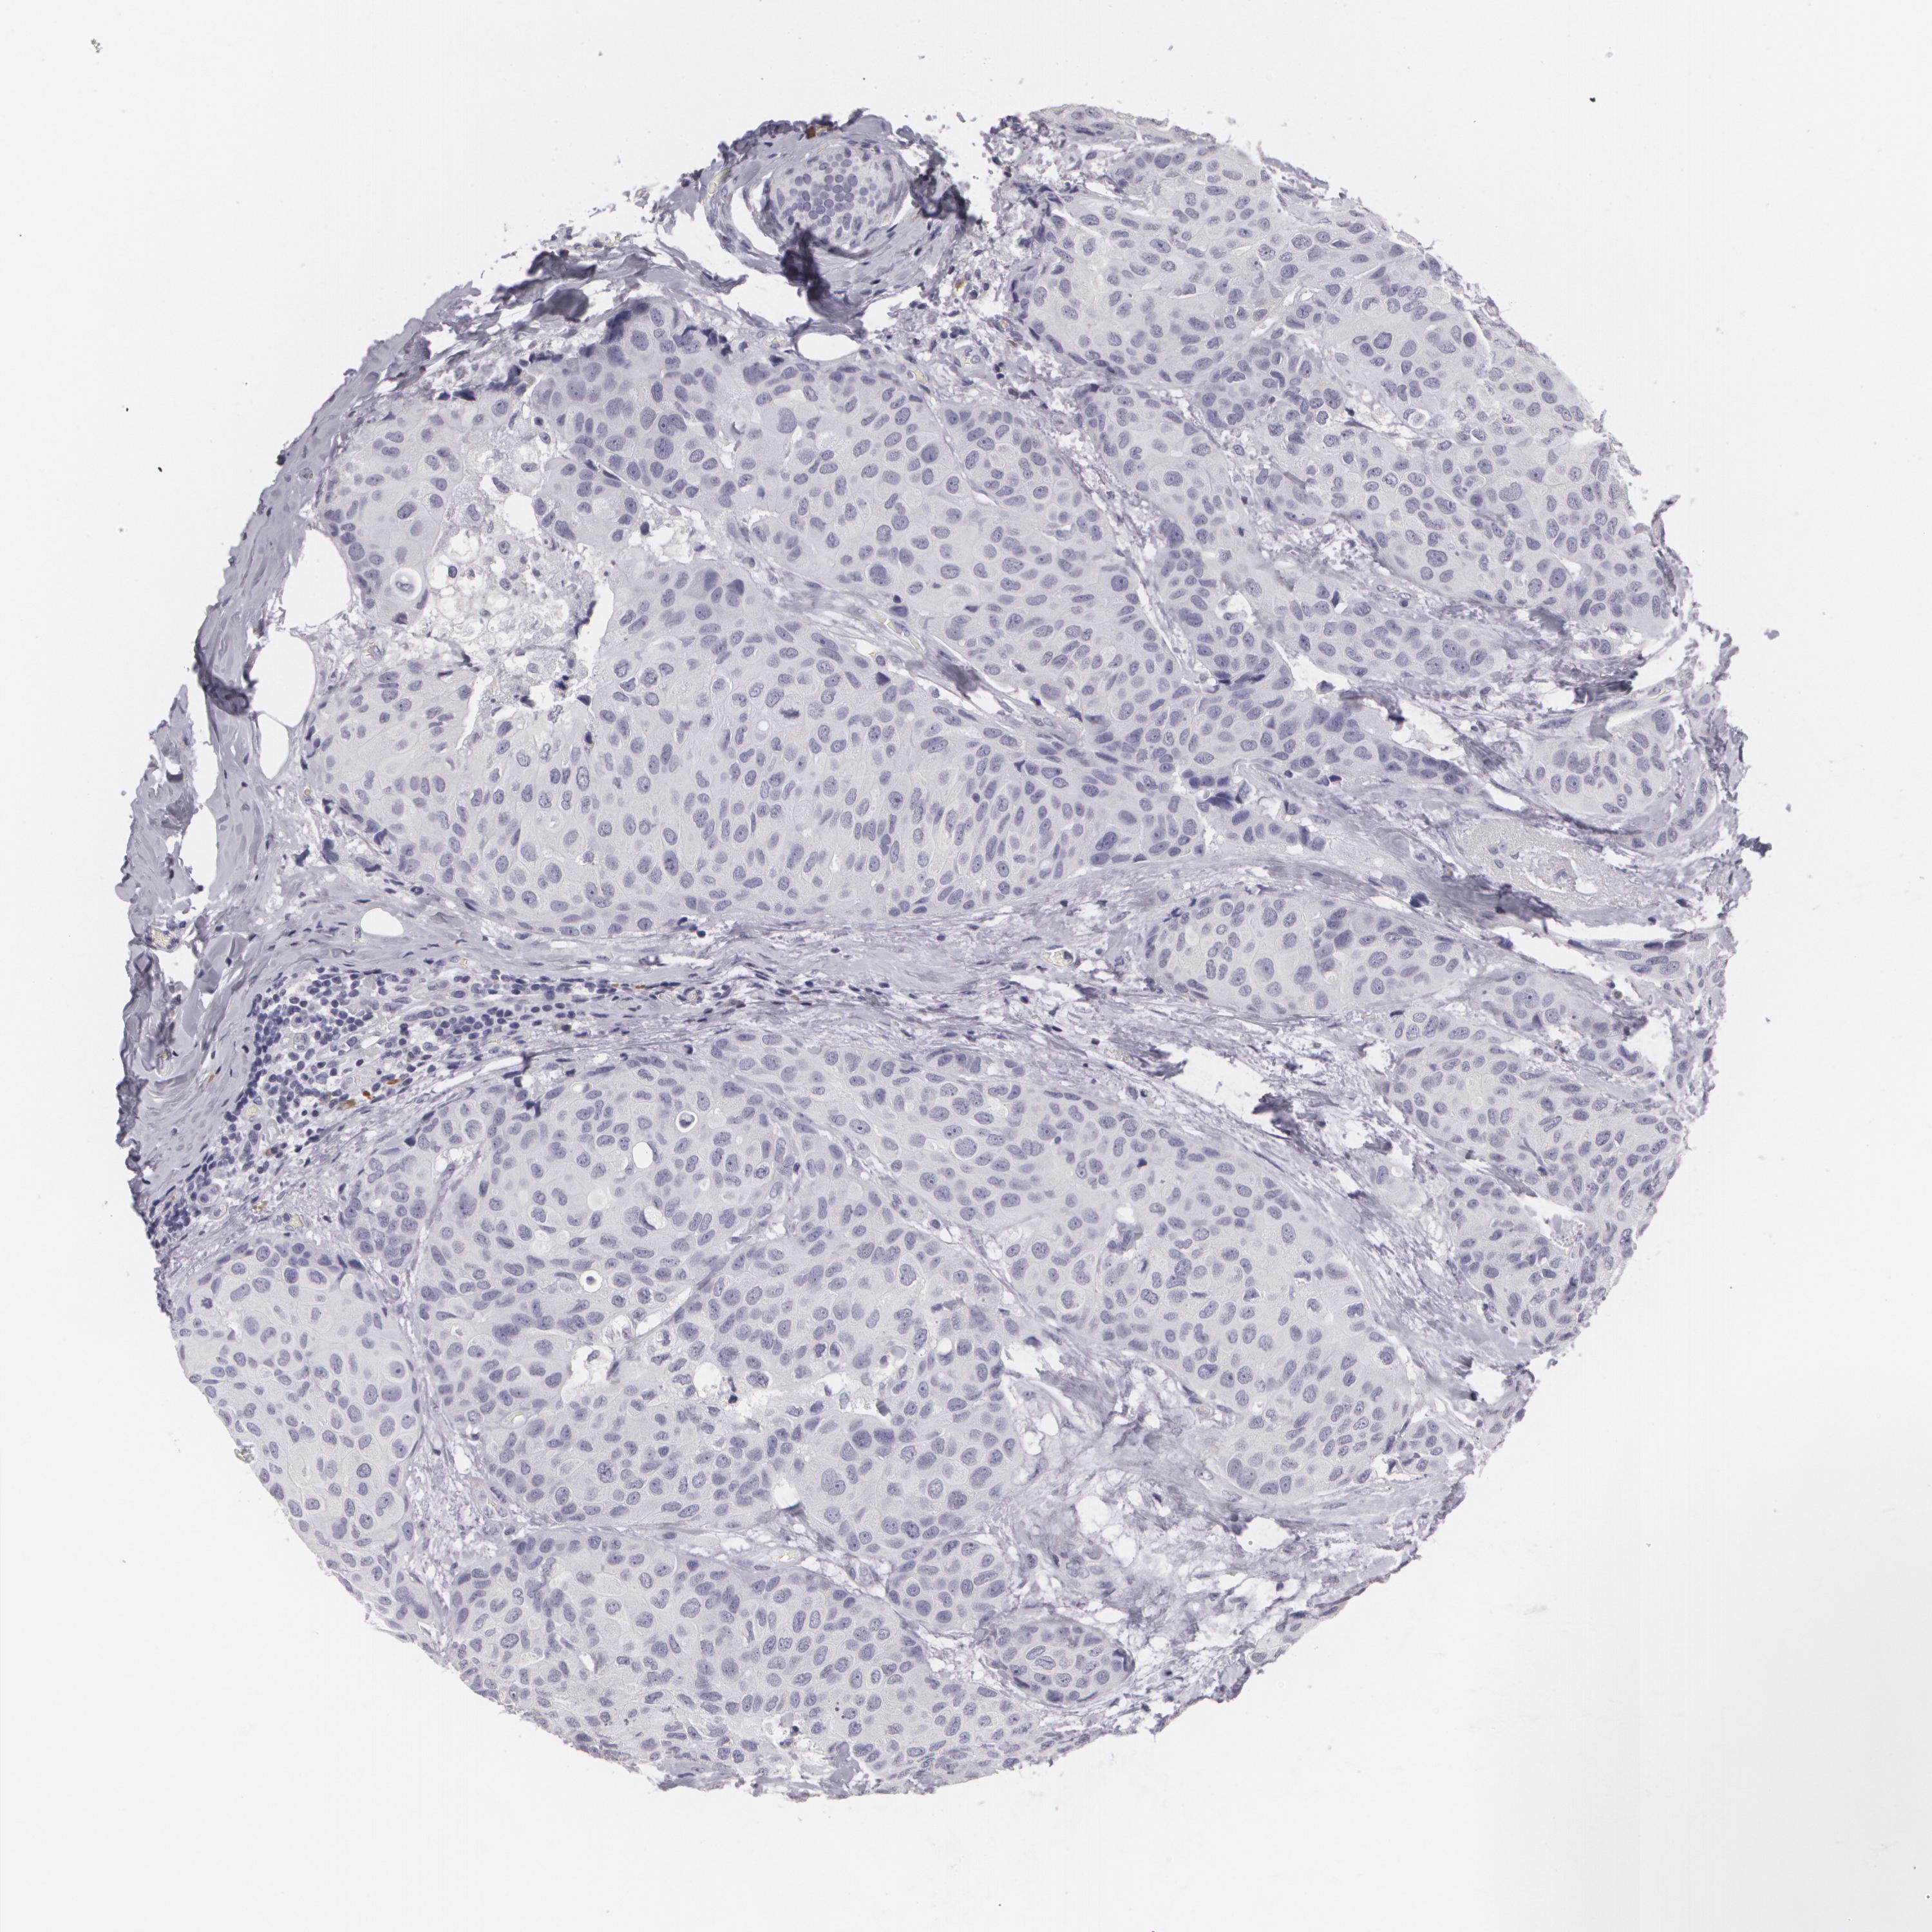

CANCER BREAST CANCER Show tissue menu

BRCA TCGA BRCA VALIDATION PROTEIN EXPRESSION

Breast cancer

Human cancer